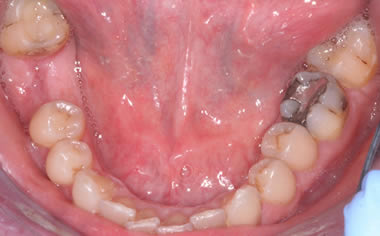

More back teeth replaced by dental implants

Case Four (4 images)